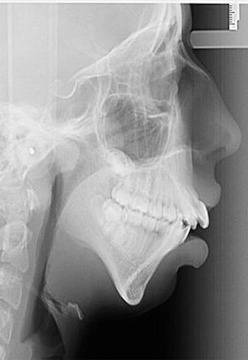

Децата са искрени същества, които нямат задръжки. Те са жестоки до наивност и могат да причинят фатални последици за психиката на съученици и приятели. Това момиче се ражда с тежко изкривяване на челюстта, което и причинява ред неудобства като пълно лишение от твърда храна и невъобразими подигравки от съучениците й! „Изрод“, крокозъбел“ и какво ли още не са сред редовните обиди за нея.Днес обаче..

Подлага се на ортодонтско лечение, което продължава до завършването й. Резултатът е феноменален! Днес тя може да се похвали с 24-каратова усмивка и дори успява да сбъдне мечтата си – да бъде фотомодел! Споделя, че й предстоят важни снимки за една от топ компаниите в света на модата.